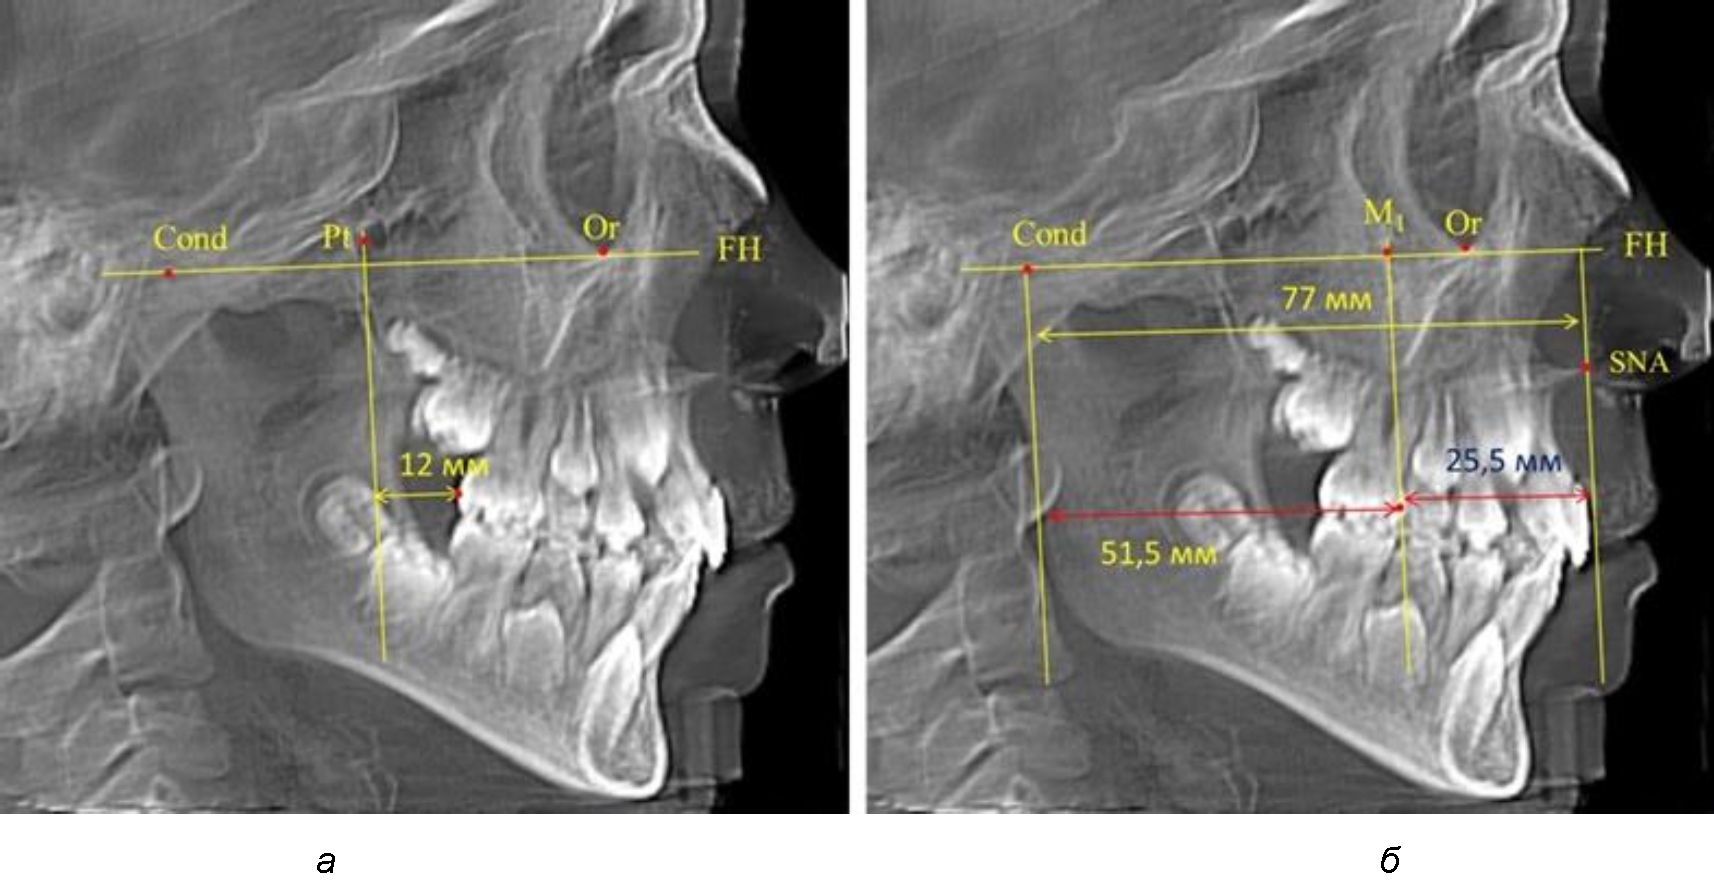

При проведении анализа к Франкфуртской горизонтали проводили передний и задний перпендикуляры. Передний спинальный перпендикуляр проходил через выступающую точку передней носовой ости (spina nasalis anterior – SNA), а задний суставной перпендикуляр опускали из кондилярной точки Cond. Молярный перпендикуляр проводили через медиальную поверхность первого постоянного моляра. Указанная вертикаль отделяла замещающие зубы постоянного прикуса от добавочных зубов (постоянных моляров), что вполне логично для анализа положения первых постоянных моляров в гнатическом комплексе (рис. 1).

Рис. 1. Метод определения положения первых верхних моляров по Ralph E. McDonald (а) и по предложенному методу (б)

Среди анализируемых рентгенограмм минимальное значение расстояния по методу R. E. McDonald было 12 мм, а максимальное достигало 25 мм, что, по нашему мнению, обусловлено вариабельностью сагиттального размера гнатического отдела лица.

Так, при расстоянии от крыловидной вертикальной плоскости PTV до дистальной поверхности верхнего первого постоянного моляра в 13 мм сагиттальный размер гнатического отдела был 82 мм. При этом отношение кондилярно-спинального расстояния к кондилярно-молярному размеру (54,5) было близким к коэффициенту 1,5, что представлено на рис. 2.